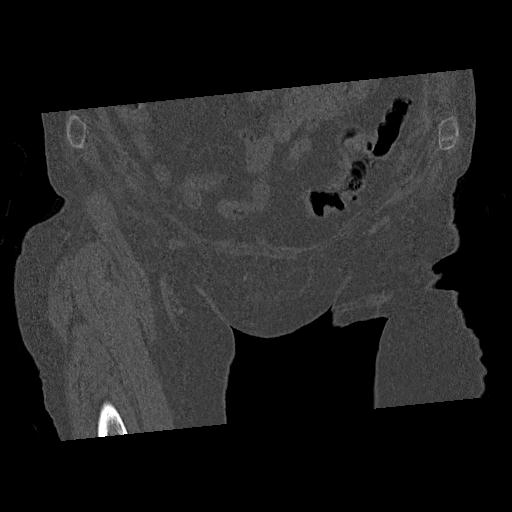

100703 1/27 両股正面+軸 1/29 両股正面+軸 94歳女性 パンソンロン

46666 1/28 両股正面+軸と 1/26 右手関節 2R 76歳女性 右転子部骨折

37 1/18 両股正面+軸 1/22 2R 86歳女性 右転子下

91569 3/25 両股正面とラウエン 70歳女性 人工骨頭+バンクーバー